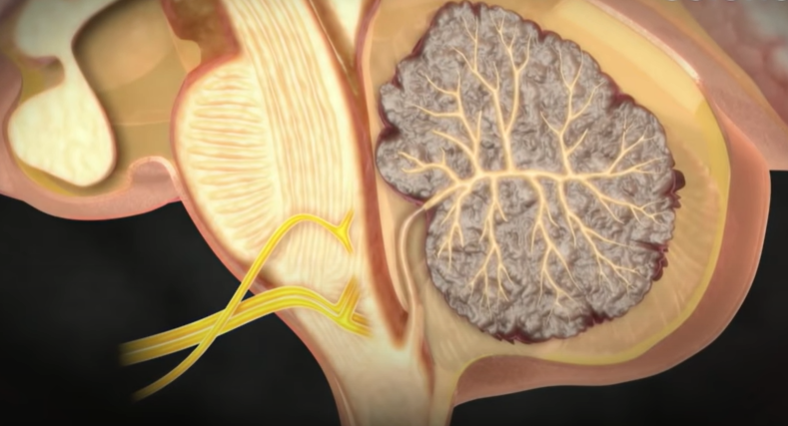

해리성 뇌동맥류

뇌혈관은 총 3겹의 층으로 이뤄져 있는데, 안쪽에 있는 혈관 벽이 찢어지면,

피가 그 사이로 흘러 마치 뇌동맥류처럼 부풀어 오른다.

동맥을 단단히 감싸고 있는 층이 찢어지면 동맥을 감싸는 힘이 없어지기 때문에 동맥의 일부가 밖으로 튀어나오게 된다. 그러면서 동맥류의 형태로 불룩하게 꽈리처럼 생기는 것을 해리성 뇌동맥류라 한다. 기본적으로 동맥 박리가 먼저 일어나고, 동맥의 모양이 쭈글쭈글해진다든지 내피세포가 손상되어 동맥이 막혀 뇌경색이 생기거나 또는 동맥의 해리(떨어져 나감)가 밖으로 진행돼서 동맥을 싸고 있는 외피가 찢어지면 밖으로 출혈이 생긴다.